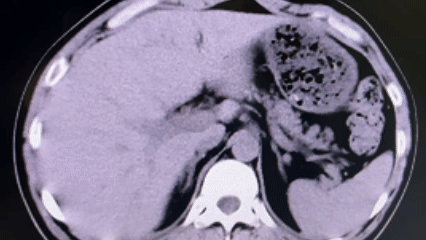

图片

在与患者及家属进行充分沟通,并获得手术同意后,医疗团队为患者实施了“经皮肾镜下右肾结石碎石取石术+经尿道输尿管支架管置入术”。术中,医生顺利穿刺、碎石,成功清除了困扰患者的结石;麻醉医生全程严密监护,确保生命体征平稳;护理团队默契配合,为手术的顺利进行提供了坚实保障。